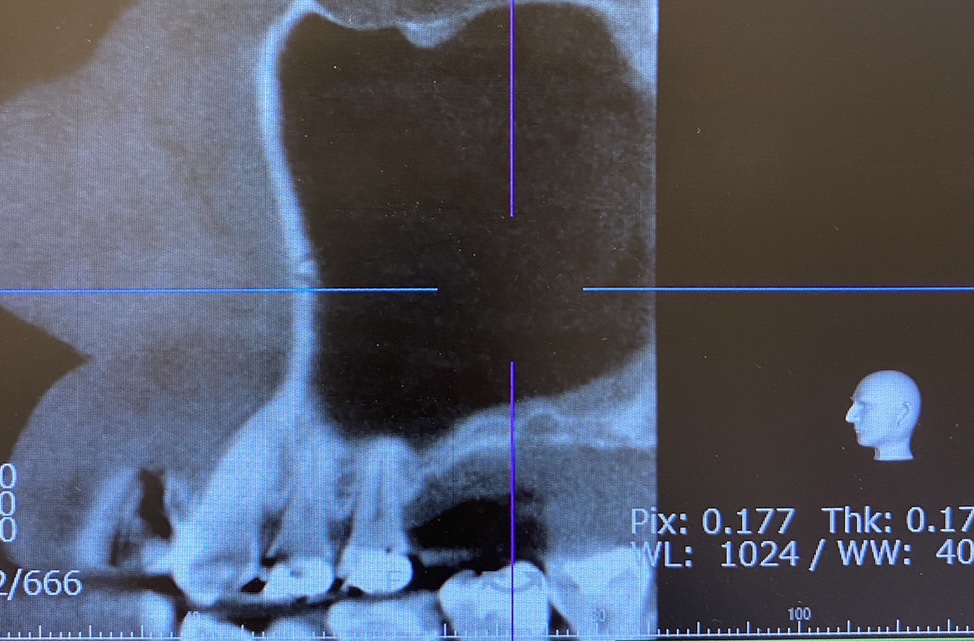

After

上顎の骨が少なく、インプラントを行えないためサイナスリフト(骨造成)をおこないました。

当院でサイナスリフトを行い、かかりつけの元の医院でインプラント治療を行う予定です。

| 症例名 | 上顎の骨造成(サイナスリフト) |

| 治療内容 | サイナスリフト | ||||

| 費用 | 27.5万円 | ||||